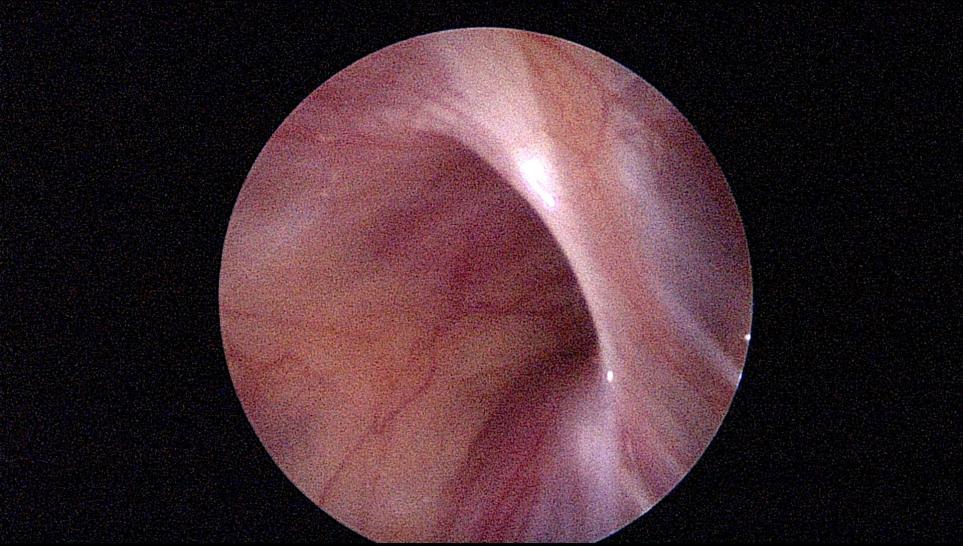

手术过程中的情况

2mm腹腔镜下单孔手术切口